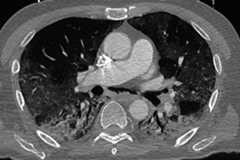

At admission, the patient was dehydrated and his blood glucose level was 30 mmol/L (normal range 3.9–5.8 mmol/L). His body temperature was normal. Within a few hours, his oxygen saturation level dropped from 93% to 50% and he was immediately admitted to the isolation ward and intubated. He was given ceftriaxone, clarithromycin and piperacillin/tazobactam (2×500 mg intravenous). CT from the lung revealed multifokal bilateral ground glass infiltrates at the periphery of the upper lobes with involvement of the right middle lobe suggesting bilateral interstitial pneumonia (figure 1).3 In addition, there were infiltrates with a positive bronchogram in both lower lobes and a pneumomediastinum, not typical for interstitial pneumonia. There were no pleural effusions.

Figure 1.

Multifocal bilateral ground glass infiltrates at the periphery of the upper lobes with involvement of the right middle lobe and consolidation in both lower lobes.